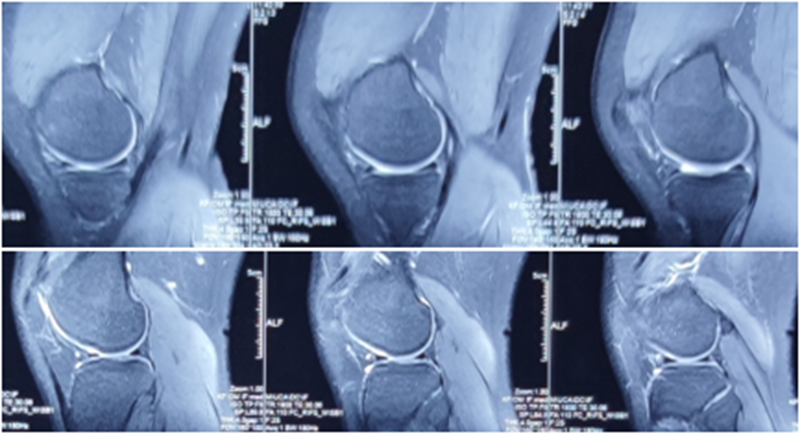

典型病例,张X,男,18岁,因扭伤致左膝关节疼痛伴活动受限1月余入院。

诊断:1.左膝前交叉韧带损伤;2.左膝外侧半月板损伤合并囊肿。

手术方案:左膝关节镜下清理、滑膜切除、外侧半月板部分切除成形、前交叉韧带重建术。

术前MRI

术后MRI